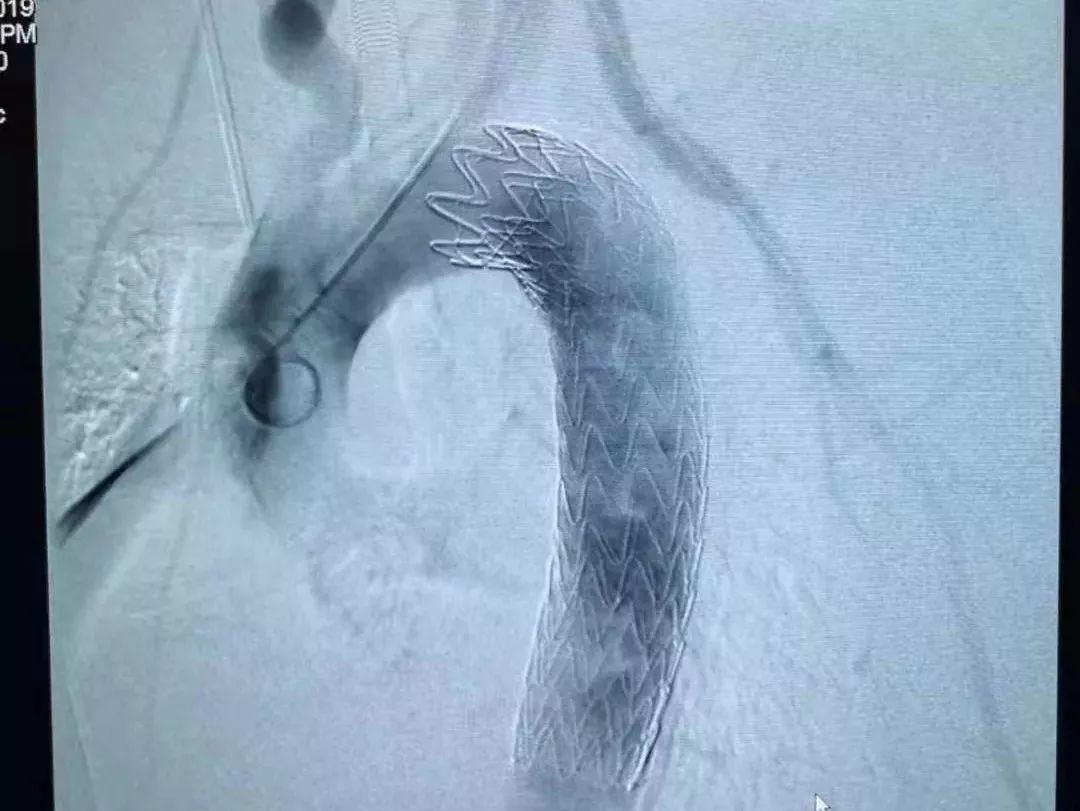

去医院CTA检查发现,一根鱼刺样的异物卡在了食管内,且已刺穿食管壁,一头已经扎进了胸主动脉。

11月29日,林先生来到了武汉大学人民医院急诊科就诊。魏捷教授检查发现,鱼刺像一把圆月弯刀,横插在食管和胸主动脉附近。如果盲目拔出,必定会形成主动脉破口,发生大出血。

手术台上,专家团队判断很有可能是由于食道的蠕动,或是主动脉内血流的强劲冲击,这根鱼刺已经穿出食管进入胸腔甚至主动脉了。

手术方案立即调整。医生从右侧开胸探查胸腔,发现鱼刺果然是穿出了食管,几乎整个扎进了主动脉内,仅在外露出3毫米的刺尖。